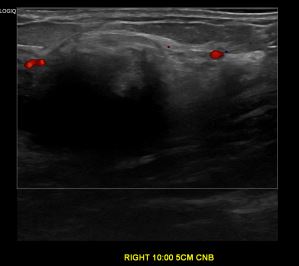

상기환자 유방에 만져지는 멍울있어 검사위해 내원하신 60대 여성분으로 의심스러운

우측유방 혹 총조직검사 시행해 유방암 진단되었습니다